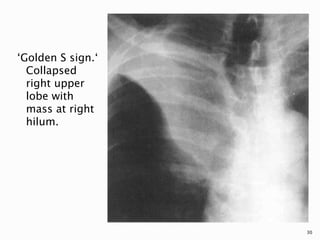

 Occasionally, the cancer remains

identifiable as a central contour bulge, and

if it obstructs the right upper lobe

bronchus, it may result in the S-sign of

Golden.

‘Golden S sign.‘

Collapsed

right upper

lobe with

mass at right

hilum.

30